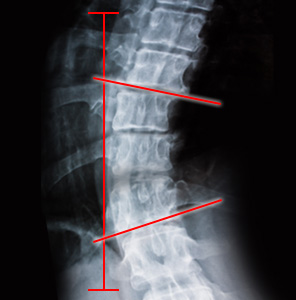

척추 측만증은 척추가 정면에서 보았을 때 옆으로 휜 것을 지칭하긴 하지만, 실제로는 단순한 2차원적인 기형이 아닌 척추 자체의 회전 변형과 동반되어 옆에서 보았을 때에도 정상적인 만곡 상태가 아닌 3차원적인 기형 상태를 말합니다. 검사는 방사선 촬영을 이용해 상담해드리고 있습니다.